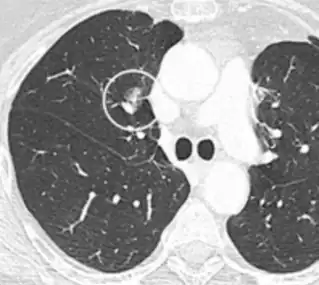

• Location: Upper lobe location is a risk factor for cancer, while a location close to a fissure or the pleura indicates a benign lymph node,[8] especially if having a triangular shape.[9]

• Margin morphology: a spiculated margin is a risk factor for cancer.[8] Benign causes tend to have a well defined border, whereas lobulated lesions or those with an irregular margin extending into the neighbouring tissue tend to be malignant.[10] In particular, spiculations are highly predictive of malignancy with a positive predictive value up to 90%.[9] Also, a "notch sign", which is an abrupt indentation of the nodule, increases the risk of cancer, but may also be found in granulomatous diseases.[9]

Calcifications and popcorn-like appearance, conferring a diagnosis of hamartoma.[9]

• In case of calcifications, a popcorn-like appearance indicates a hamartoma, which is benign.[3]

• Pleural retraction is far more common in cancers.[9] It is the pulling of visceral pleura towards the nodule.[9]

Lung nodule abutting a pulmonary cyst.[9]

• A lung nodule abutting a pulmonary cyst is a rare finding, yet indicating cancer.[9]

• Bubble-like lucencies in the nodule indicate cancer:[9]

Thin slice and maximal intensity projection of a lung nodule, the latter better visualizing vascular convergence.[9]

• Vascular convergence is where vessels converge to a nodule without adjoining or contacting the edge of the nodule, and is mainly seen in peripheral subsolid lung cancers.[9] It reflects angiogenesis.[9]